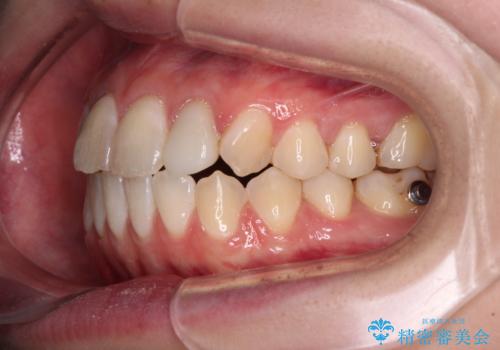

開咬を治す インビザラインによる矯正治療

- 上下前歯の開咬を気にして来院された患者様です。

開咬はインビザラインを用いると有意に改善ができるため、インビザラインによる矯正治療を行うこととしました。

途中1年8ヶ月ほど来院されず、久しぶりの来院後は治療が面倒とのことで、前歯の叢生や隙間に不十分な点が残った状態での終了となりました。